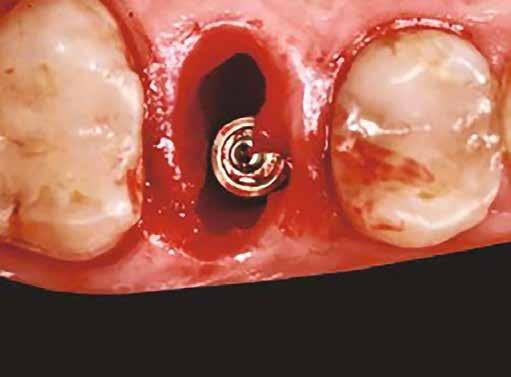

A sebészeti eljárás

Mind a hat implantátum esetén kétlépcsős műtétet végeztünk. Minden sebészeti eljárást bódítás, illetve preoperatív szisztémás antibiotikus terápia nélkül végeztünk. A négy eset közül kettőnél leukocitában és vérlemezkében gazdag fibrint (L-PRF) alkalmaztunk a beavatkozás során (IntraSpin, BioHorizons; 2. táblázat). Minden esetben a pontos CERALOG menetvágási (maximum 15 ford./perc) és fúrási (maximális fúrási fordulatszám: 550–800 ford./perc) protokollt követtük. Az összes implantátumot manuálisan helyeztük be 35 Ncm maximális nyomatékkal. Az implantátumokba PEEK zárócsavar került (2. ábra). A lágyszövetet atraumatikus, felszívódó varrattal, szorosan zártuk/összevarrtuk. A műtétek után szövődmények nem jelentkeztek. A pácienseket arra kértük, hogy a műtét utáni héten naponta kétszer öblögessenek klórhexidinnel (PERIO-AID, 0,05%, DENTAID). Az alsó állcsontnál három hónapos, a felső állcsontnál öt hónapos gyógyulási időt vettünk figyelembe. Három hónap (1. eset) és öt hónap (2., 3. és 4. eset) elteltével a műtétek második stádiumát helyi érzéstelenítés mellett végeztük. A gyógyu-

lási csavarokat (PEEK titáncsavarral) maximum 15 Ncm-rel húztuk meg (3–6. ábra). Az összes implantátum kiváló stabilitást mutatott (a mérésekhez Periotestet használtunk, a Medizintechnik Gulden jóvoltából), és teljesen osszeointegrálódott. Ezt a radiológiai vizsgálatok is megerősítették.